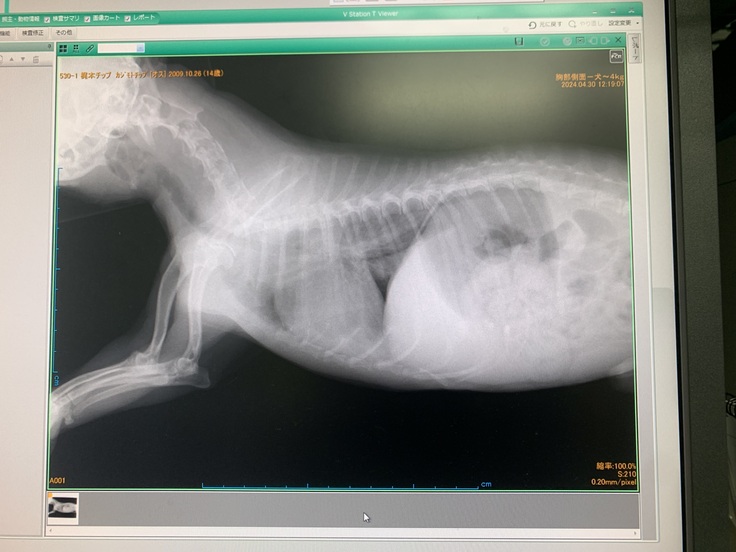

先日咳がひどくなったときのレントゲン写真です。

やはり心臓が少し大きくなり、肺炎を起こしているとのことでした。

利尿剤を再開し、今はだいぶ落ち着きました。